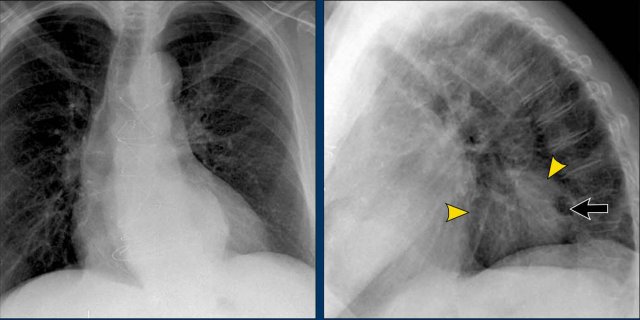

Hidden Areas (2): Right Lower Lobe Lesion

This example demonstrates a large mass in the right lower lobe that is challenging to identify on the PA view unless close attention is paid to the hidden areas.

- On initial inspection, the lesion is inconspicuous.

- However, with focused review of the subdiaphragmatic and retrocardiac regions, the abnormality becomes evident.

- Enlarge the image for better visualization.

Hidden Areas (3): Pneumonia Below the Diaphragm

In this case, a pneumonia was primarily located below the right diaphragmatic dome (yellow arrow), within the posterior basal segment of the right lower lobe.

- On the lateral view, there is an increase in opacity over the lower thoracic vertebrae, indicating lower lobe consolidation (arrow).

- Again, image magnification may be necessary for adequate assessment.